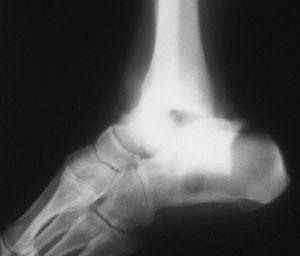

Respecto a las luxaciones del astrágalo, se han encontrado 7 casos de las cuales 5 (71,4%) de ellas eran luxaciones mediales --el pié se desplaza hacia adentro con respecto al astrágalo-- (figs. 13 y 14). La luxación medial es la más frecuentes --el 72% del total según DeLee y Curtis30 y Zimmer y Johnson31, y el 85% para Motley et al6--, seguidas de las laterales (de peor pronóstico) y mas infrecuentes las anteroposteriores.

Fig. 13. --Enucleación del astrágalo. Reducción, desbridamiento y estabilización temporal con agujas K.

Fig. 13. --Enucleation of the astragalus. Reduction, debridement and temporary stabilisation with Kirschner needles.

Fig. 14. --A) Radiografía al sexto mes: osteoporosis. B) Radiografía a los 18 meses: artrosis tibioastragalina.

Fig. 14. --a. Radiography at 6 months. b. Radiography at 18 months: tibio-astragalar arthrosis.